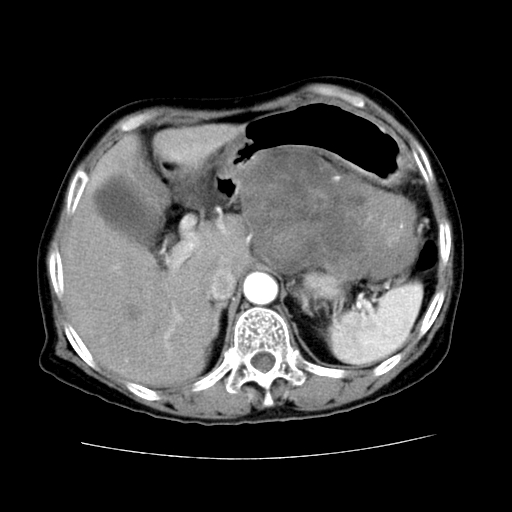

女性,72岁。

主诉中上腹部疼痛不适1年余。

胰腺尾部不规则巨大略低密度肿块,界限清楚,内密度不均,增强动脉期不均匀强化,门脉期明显退减并低于胰腺密度,肿瘤包埋于脾血管。多考虑;来源于胰腺尾部的“胰腺癌”。

胰腺尾部不规则巨大略低密度肿块,界限清楚,内密度不均,增强动脉期不均匀强化,门脉期明显退减并低于胰腺密度,肿瘤包埋于脾血管。多考虑;来源于胰腺尾部的“胰腺囊腺癌。

1、这个病例确实有点难。影像主要显示胰腺体尾部占位,我们当初也是诊断胰体尾部囊腺癌可能性大,而且读片会上也很多人这么诊断的。

2、手术所见:打开腹腔发现胃与胰腺体尾部可见肿块,大小约10×8×11cm,质硬,不可推动,周围血供丰富。术中诊断:胃肿瘤侵及胰腺体尾部。

1)、胃小弯侧胃肠间质瘤(考虑恶性),瘤体大小13.5×7×6.5cm,上下切缘阴性。

2)、胃小弯1只、幽门下2只淋巴结慢性炎。免疫组化:cd117(+)、cd34(+)、sma(+)、desmin(-)、s-100(-)、ki-67<10%(+).

4、这个肿瘤太大了,而且密度不均性强化,从这点我们应该不能单纯诊断胰腺癌,而应想到目前流行的胃肠道间质瘤。这个肿瘤主要发生于胃壁浆膜层,所以显示与胃壁关系不是很紧密,故而大多认为是胰腺癌。

谢谢反馈结果,如楼主分析,本病例主要肿块与胃壁见有分界,而与胰腺分界不清,故而首先考虑胰腺肿瘤。